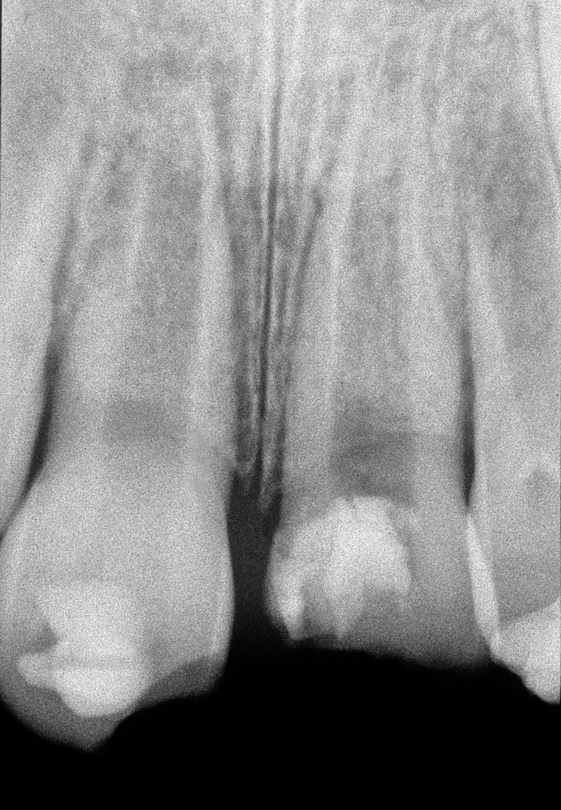

Fig 12. Age 9. Radiograph of teeth Nos. 8 and 9 at initial examination. Orthodontic brackets were placed to stabilize the teeth.

Figure 12

Teeth Nos. 7 through 10 were included in the endodontic examination. Nos. 7 and 10 responded to cold; there was no response to cold or electric pulp test (EPT) from either tooth No. 8 or 9. All the teeth gave a mild positive response to percussion, and none of the teeth were tender to palpation. Both Nos. 8 and 9 probed within normal limits (WNL). Radiographs showed a small apical radiolucency associated with No. 8 and a widened periodontal ligament (PDL) on the mesial and apical aspect of No. 9 (Figure 12). An access was made in No. 8, and the canal was debrided and filled with Ca(OH)2.

One month later, the teeth were reevaluated. Nos. 7 and 10 continued to respond to cold. No. 8 was not mobile and sounded ankylosed when percussed. No. 9 was slightly mobile and did not respond to cold or EPT. A 3 mm x 3 mm apical lesion had formed on No. 9. Ca(OH)2 was replaced in tooth No. 8, and No. 9 was opened, debrided, and filled with Ca(OH)2. Both teeth were filled with gutta-percha 6 months after the initial endodontic examination. At that time, tooth No. 8 showed early evidence of replacement resorption on the mesial of the root; No. 9 was slightly mobile and the PDL appeared intact (Figure 13).